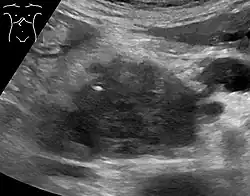

Medical imaging techniques, such as computed tomography (CT scan) and endoscopic ultrasound (EUS) are used both to confirm the diagnosis and to help decide whether the tumor can be surgically removed (its "resectability").[12] On contrast CT scan, pancreatic cancer typically shows a gradually increasing radiocontrast uptake, rather than a fast washout as seen in a normal pancreas or a delayed washout as seen in chronic pancreatitis.[58] Magnetic resonance imaging and positron emission tomography may also be used,[2] and magnetic resonance cholangiopancreatography may be useful in some cases.[34] Abdominal ultrasound is less sensitive and will miss small tumors, but can identify cancers that have spread to the liver and build-up of fluid in the peritoneal cavity (ascites).[12] It may be used for a quick and cheap first examination before other techniques.[59]

A biopsy by fine needle aspiration, often guided by endoscopic ultrasound, may be used where there is uncertainty over the diagnosis, but a histologic diagnosis is not usually required for removal of the tumor by surgery to go ahead.[12]